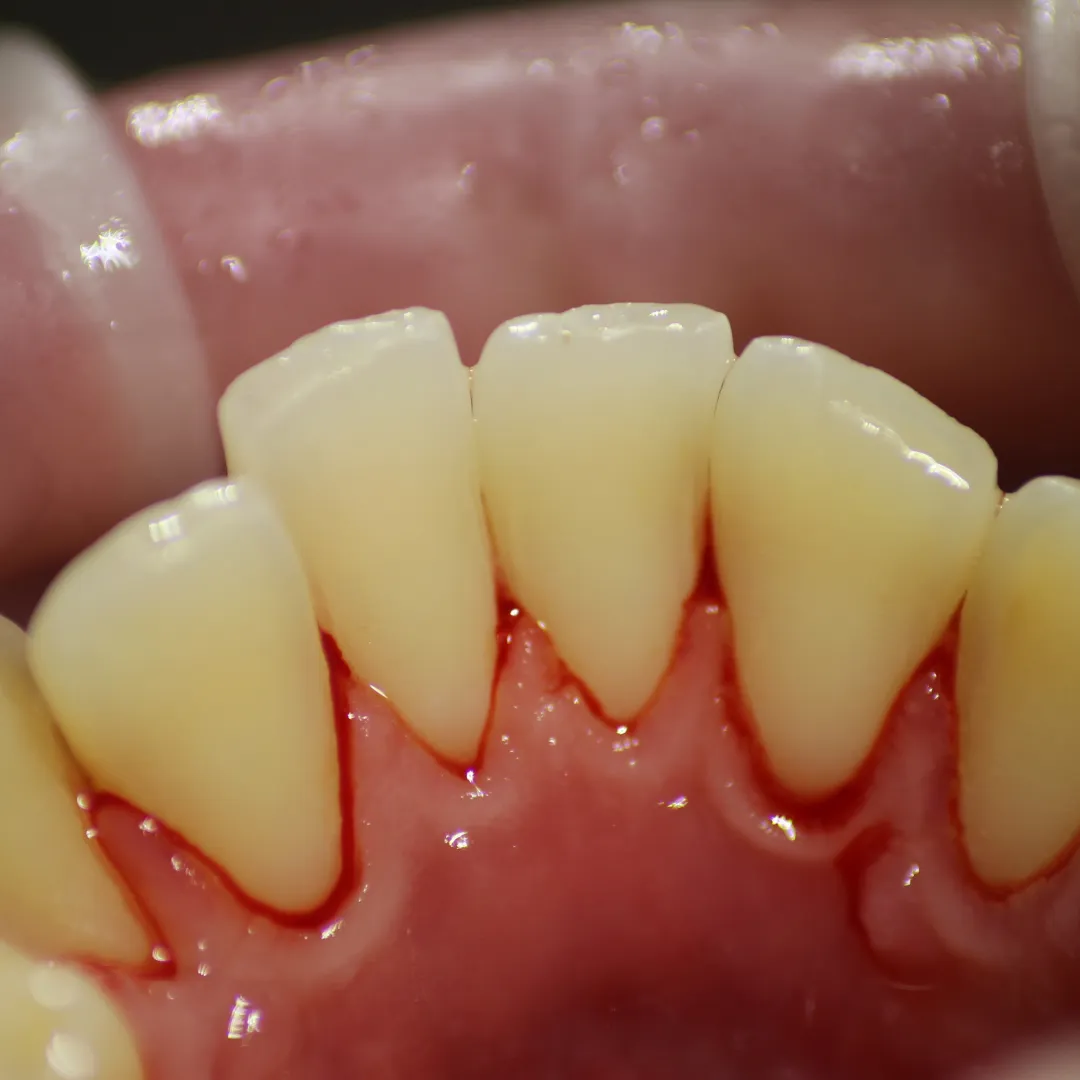

Выполнение профессиональной гигиены для снятия минерализованных зубных отложений и пигментированного налётаСмотреть работуСрок лечения:1 часСумма лечения:3 850 руб.

Процедура профессиональной гигиены для снятия минерализованных зубных отложений и пигментированного налётаСмотреть работуСрок лечения:40 мин.Сумма лечения:3 850 руб.

Процедура профессиональной гигиены для снятия минерализованных зубных отложений и пигментированного налёта.Смотреть работуСрок лечения:45 мин.Сумма лечения:3 850 руб.

Удаление десневых и зубных отложений с помощью УЗ-аппаратаСмотреть работуСрок лечения:60 мин.Сумма лечения:3 880 руб.